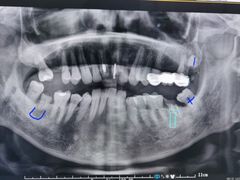

• 牙博士口腔品牌连锁(杨浦店)

• -牙博士口腔品牌连锁(杨浦店)